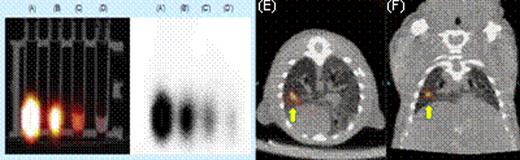

We first tested whether commercially available nanoparticles can be electro-transferred into cultured and primary human T cells. 43 nm diameter latex nanoparticles and 7 nm gold nanoparticles (GNPs) were electro-transferred into T cells and visualized by TEM and confocal imaging (Figure 1). We have modified GNPs on the surface with the chelator, diethylenetriaminepentaacetic acid (DTPA), for stable coordination with 111In followed by GNP PEGylation. We have shown that these radiolabeled GNPs can be readily electro-transferred into T cells suitable for combined single-photon emission computed tomography (SPECT) and computed tomography (CT) (Figure 2). We used a clinical SPECT/CT scanner to detect 111In-GNP in T cells (∼2.1 × 104 nanoparticles/cell) at a sensitivity of ∼760 cells/mL. After developing electroporation protocols of nanoparticles and in vivo imaging of 111In-GNPs, additional sensitivity was achieved by modifying the chelating chemistry using the macrocyclic chelator, 1,4,7,10-tetraazacyclododecane-1,4,7,10-tetraacetic acid (DOTA), to bind 64Cu to GNPs, increasing the number of gold particles/cell, and using 64Cu-labeled GNPs for imaging by positron emission tomography (PET). Before tail vein injection to a mouse, 11.4 mCi was detected from 10 million T cells (suspended in 300 μL PBS) electroporated using a BTX ECM830 device with the following settings: 1 kV/cm, 4 ms duration, single square pulse (Figure 3). The estimated concentration of nanoparticles transferred into T cells was ∼2.3 × 105 nanoparticles/cell as determined by a gamma counter (2470 Wizard, PerkinElmer) and nanoparticle titration. While 20 nm GNPs were used for 111In labeling, 7 nm GNPs were chosen for 64Cu labeling because of the improved (10-fold) electroporation efficiency.

SPECT Imaging. (A) through (D) show the radioactivity of electro-transferred 111In-GNPs into T cells. (E) axial and (F) coronal views of directly injection of T cells containing111In-GNPs.